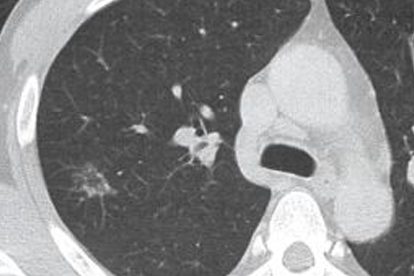

大葉性肺炎的特征性表現是病變累及整個肺葉或多個肺葉,病變界限清晰。這與小葉性肺炎的斑片狀分布形成明顯對比。胸片檢查可見均勻致密的實變陰影,與肺葉解剖分布一致。這種廣泛性病變可導致嚴重通氣/血流比例失調,患者可能出現明顯低氧血癥。